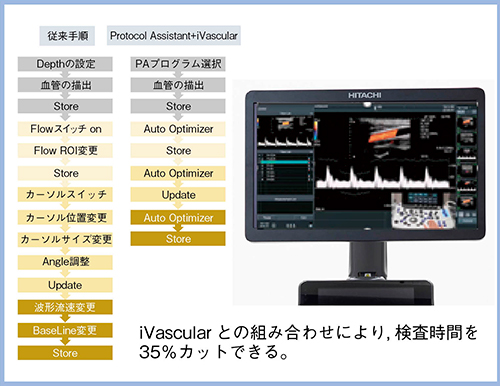

1.Protocol AssistantとiVascular

“Protocol Assistant”は,検査プロトコールをあらかじめ登録できる機能である。検査中のボタン操作などの手間を大幅に削減できるほか,画面上に検査項目が一覧でわかりやすく表示されるため,客観的かつ取りこぼしのない検査を短時間で効率良く行うことができる(図3)。

“iVascular”は,カラードプラの関心領域,カーソルの位置・幅・補正角度の4つの設定がワンボタンで自動的に調節される機能で,理想的なパルス波形が描出される(図4)。Protocol Assistantと組み合わせることで検査時間を大幅に短縮できる非常に優れた機能である。

図3 Protocol Assistantの概要